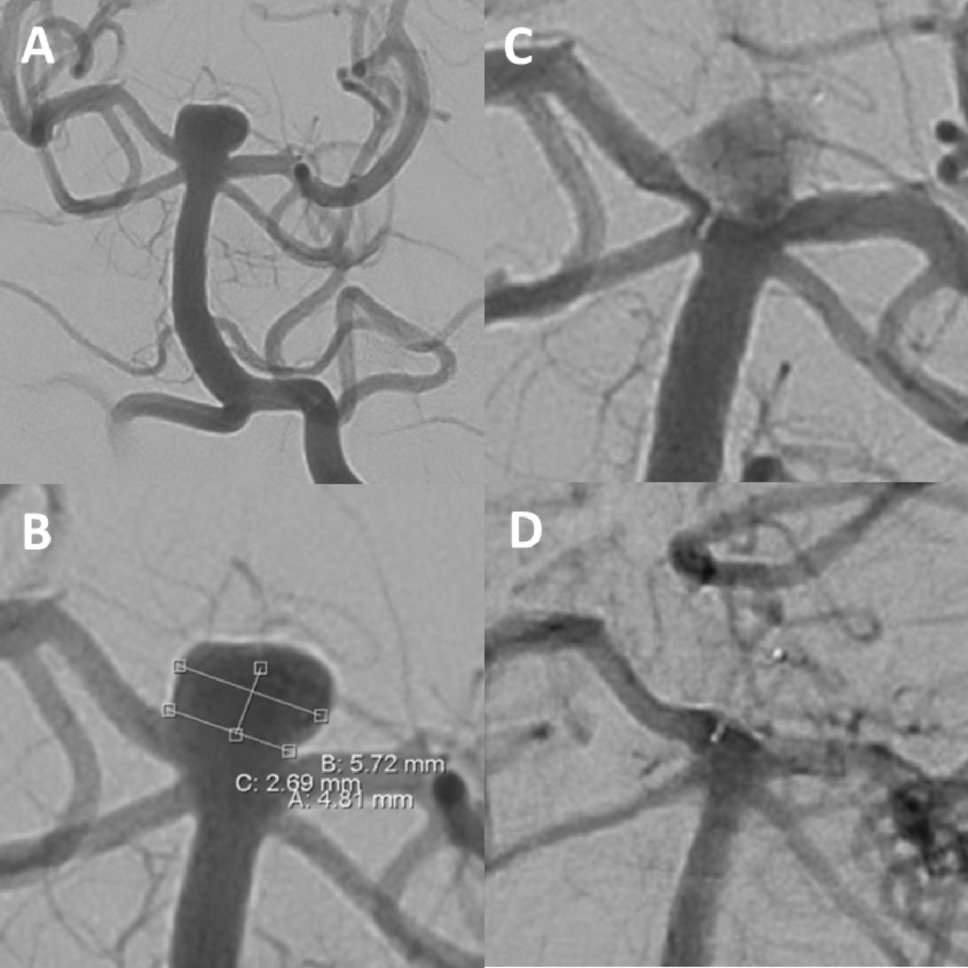

Figure 3

Unruptured aneurysm at the basilar tip (A + B). Due to the broad-based geometry and the unruptured aneurysm status, intrasaccular flow-disruption was envisaged. A WEB SL (7 × 3 mm) was placed within the aneurysm sac, achieving immediate contrast stasis (C). Two-years angiographic control shows complete aneurysm occlusion (D).